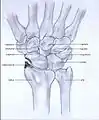

X-rays

Radiographs can confirm the diagnosis of wrist osteoarthritis. The earliest sign is narrowing of the joint space between the radius and the scaphoid and an osteophyte off the tip of the radial styloid. [9]

SLAC

Because SLAC results from scapholunate ligament rupture, there is a larger space between the two bones, also known as the Terry Thomas sign.[10] Scaphoid instability due to the ligament rupture can be stactic or dynamic.[11] When the X-ray is diagnostic and there is a convincing Terry Thomas sign it is a static scaphoid instability. When the scaphoid is made unstable by either the patient or by manipulation by the examining physician it is a dynamic instability.[11]

SNAC

In order to diagnose a SNAC wrist you need a PA view X-ray and a lateral view X-ray. As in SLAC, the lateral view X-ray is performed to see if there is a DISI.[12] Computed tomography (CT) or Magnetic Resonance Imaging (MRI) are rarely used to diagnose SNAC or SLAC wrist osteoarthritis because there is no additional value.[7] Also, these techniques are much more expensive than a standard X-ray. CT or MRI may be used if there is a strong suspicion for another underlying pathology or disease.[7]